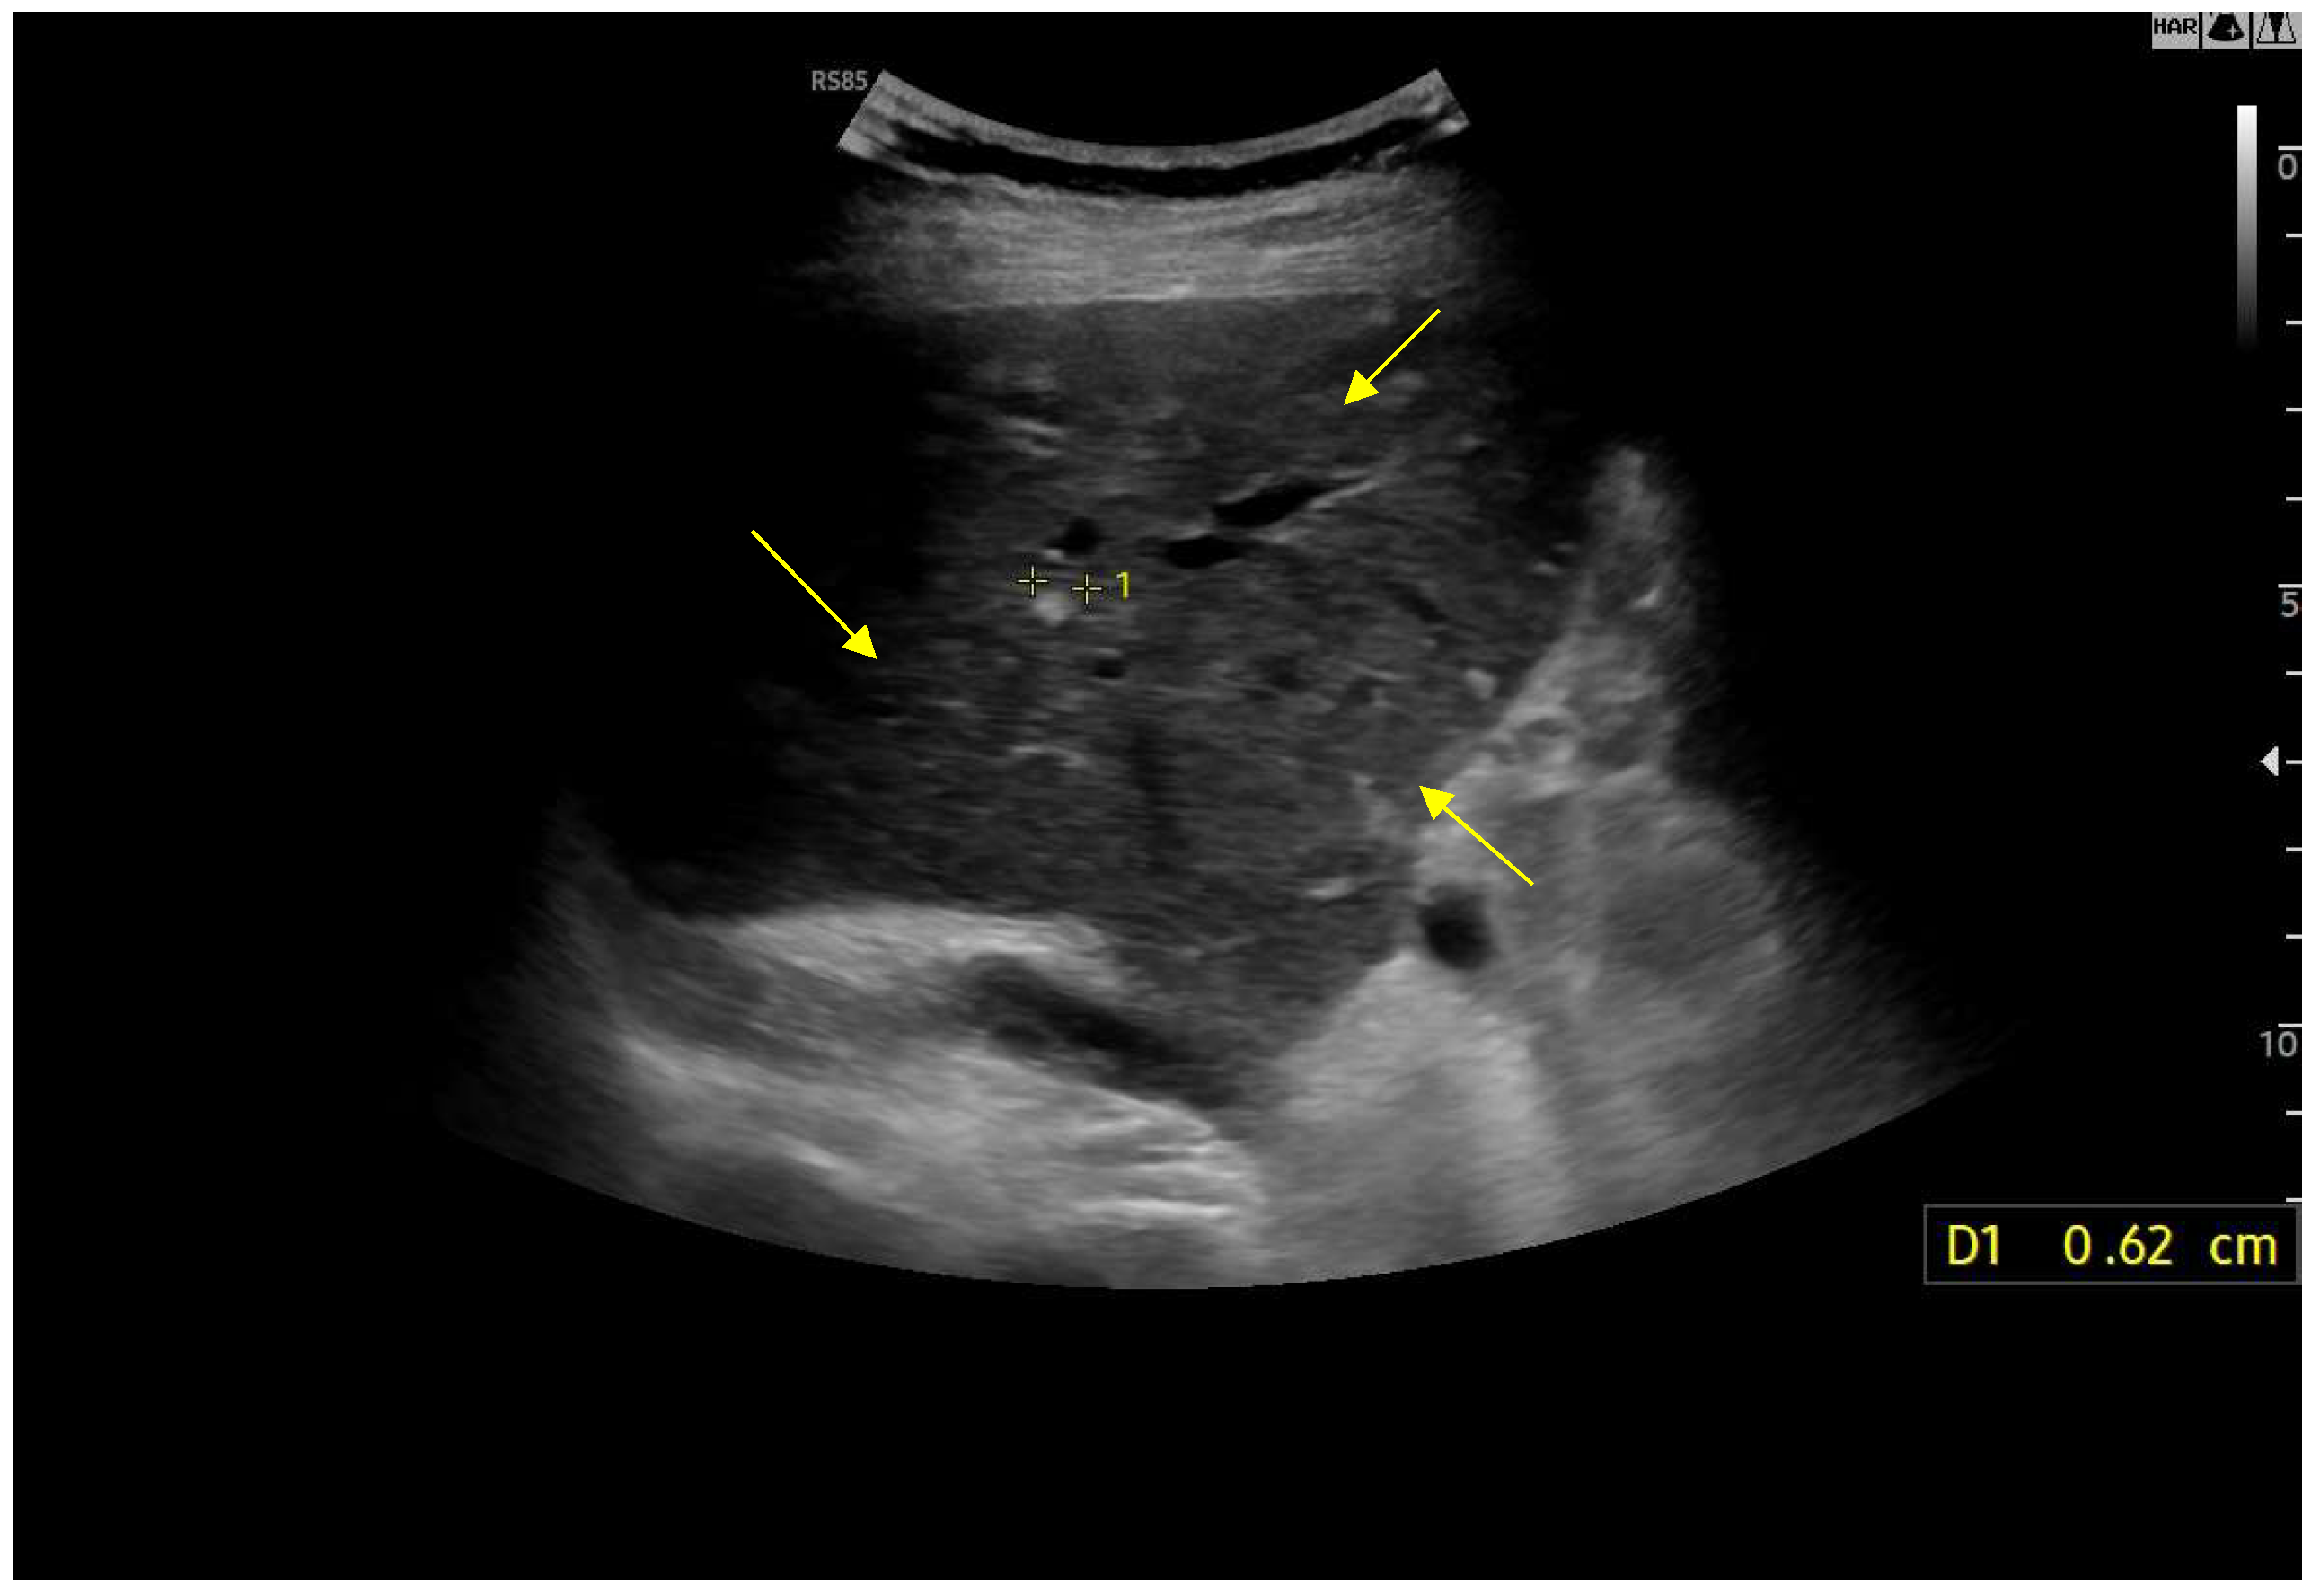

Figure 14.

Contrast-enhanced ultrasound (CEUS) in the late phase shows the appearance of hypo-vascular areas due to varying degrees of congestion and hepatic alteration. These areas may mimic malignant nodular lesions with early washout.

Figure 15.

CEUS exam showing late heterogeneous enhancement in the arterial phase with evidence of hypo-enhanced areas, thus mimicking a malignant wash-out.